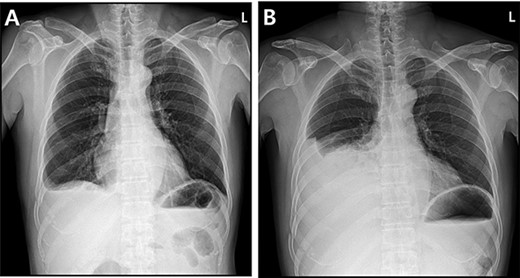

A 59-year-old man was admitted with multiple rib fractures and liver contusion due to a fall injury. He was standing on a chair for working at a farm, and it was knocked over causing him to fall and hit his flank against the corner of the chair. There was continuous pain while resting at the right flank and severe pain with pressure was noted, but no external wounds or bruises were observed. There were right 7th–11th rib fractures, scanty pneumothorax, minimal hemothorax and a 2-cm-sized liver contusion in abdomen and chest computed tomography (CT) scan (Fig. 1A, B). He was hospitalized for pain control and close observation in the general ward, and conservative management was initiated. Also, no significant changes were noted in the following daily follow-up chest radiographs. The patient suddenly complained of right-sided chest and back pain aggravation, cold sweating and fatigue 80 h after the traumatic injury. His mental status was alert, but v/s including systolic blood pressure (SBP) of 100–120 mmHg, heart rate (HR) of 40-60 beats/min and oxygen saturation of 100% during the admission changed to an SBP of 86/60 mmHg, HR of 88 beats/min and oxygen saturation of 97% when the symptoms occurred. Chest radiography was performed after the patient experienced aggravated symptoms, such as right-sided flank pain, cold sweating and fatigue. Compared to the previous scans, signs of increased opacification and peribronchial and parenchymal infiltrations were observed, which were indicative of hemothorax (Fig. 2A, B). We performed enhanced dynamic chest CT to identify any presence of active bleeding. On the chest CT scan, a large amount of hemothorax was identified in the right lung field along with multiple fractures of the right ribs. However, there were no signs of contrast leakage indicative of active bleeding (Fig. 3). Hemoglobin levels decreased from 13.1 g/dl on the day before the symptoms appeared to 11.5 g/dl at the onset of symptoms and to 9.4 g/dl after 2 h. Four packs of RBC transfusion and fluid were administered to the patient, and he was moved to the intensive care unit for close monitoring. And tube thoracostomy was performed, and 1600 ml of fresh blood was drained (Fig. 4A). The following day, 500 ml of blood was drained through the chest tube, but his v/s were stable (Fig. 4B). The amount of bleeding through the chest tube was decreased, but the drained fluid was fresh blood. And we thought that the remaining hematoma was not effectively drained, so the patient’s respiratory discomfort could persist and cause uneffective ventilation. And then we consulted with the Department of Thoracic Surgery, and video-assisted thoracoscopic surgery (VATS) exploratory thoracotomy was performed to identify the bleeding source caused by displaced rib and evacuate the large amount of hematoma. There was a large volume of hematoma within the pleural space and between the right lower lobe, diaphragm and fissure, but no active bleeding point was located. The fractured right 10th rib pierced through the pleural space and was displaced to the thoracic cavity, which was easily reduced. There was no injury surrounding the diaphragm, and although the general lung and chest wall contusions were severe, there were no signs of lung parenchymal lacerations (Fig. 5A–C). Chest tube drainage was serous, and there was no further bleeding. There were no signs of bleeding or any other abnormal findings on chest CT performed at the outpatient clinic, and the patient had no complaints of any symptoms (Fig. 6A, B).

Radiographic findings. (A) Initial chest X-ray showed no evidence of hemothorax. (B) Initial chest CT also showed no evidence of hemothorax.